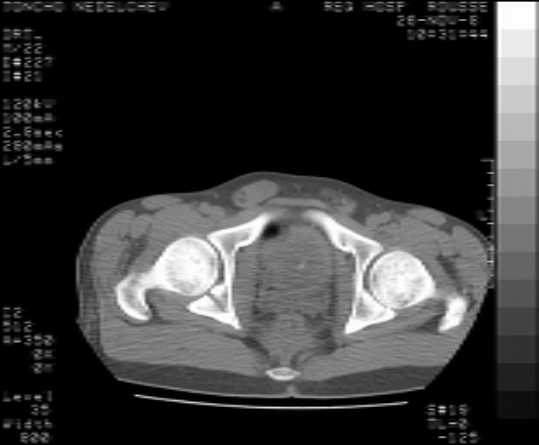

I would like to present a case of a young (22 yo) male who suffered a car crush. He has combined transverse and posterior wall fracture of the right acetabulum as well as a nondisplaced fracture of the left acetabulum and bimalleolar fracture of the left ankle. Initially we did a combined lateral and axial traction to the right leg . The patient is stable now ( 6 day after the accident ), so I would like to ask for your opinion for the best course of treatment of the right acetabulum.

Имя     : ct1.jpg

Тип     : image/jpeg

Размер  : 13413 байтов

Описание: отсутствует

Url     : http://weborto.net:8080/pipermail/ortho/attachments/20081201/e5342079/attachment-0007.jpg